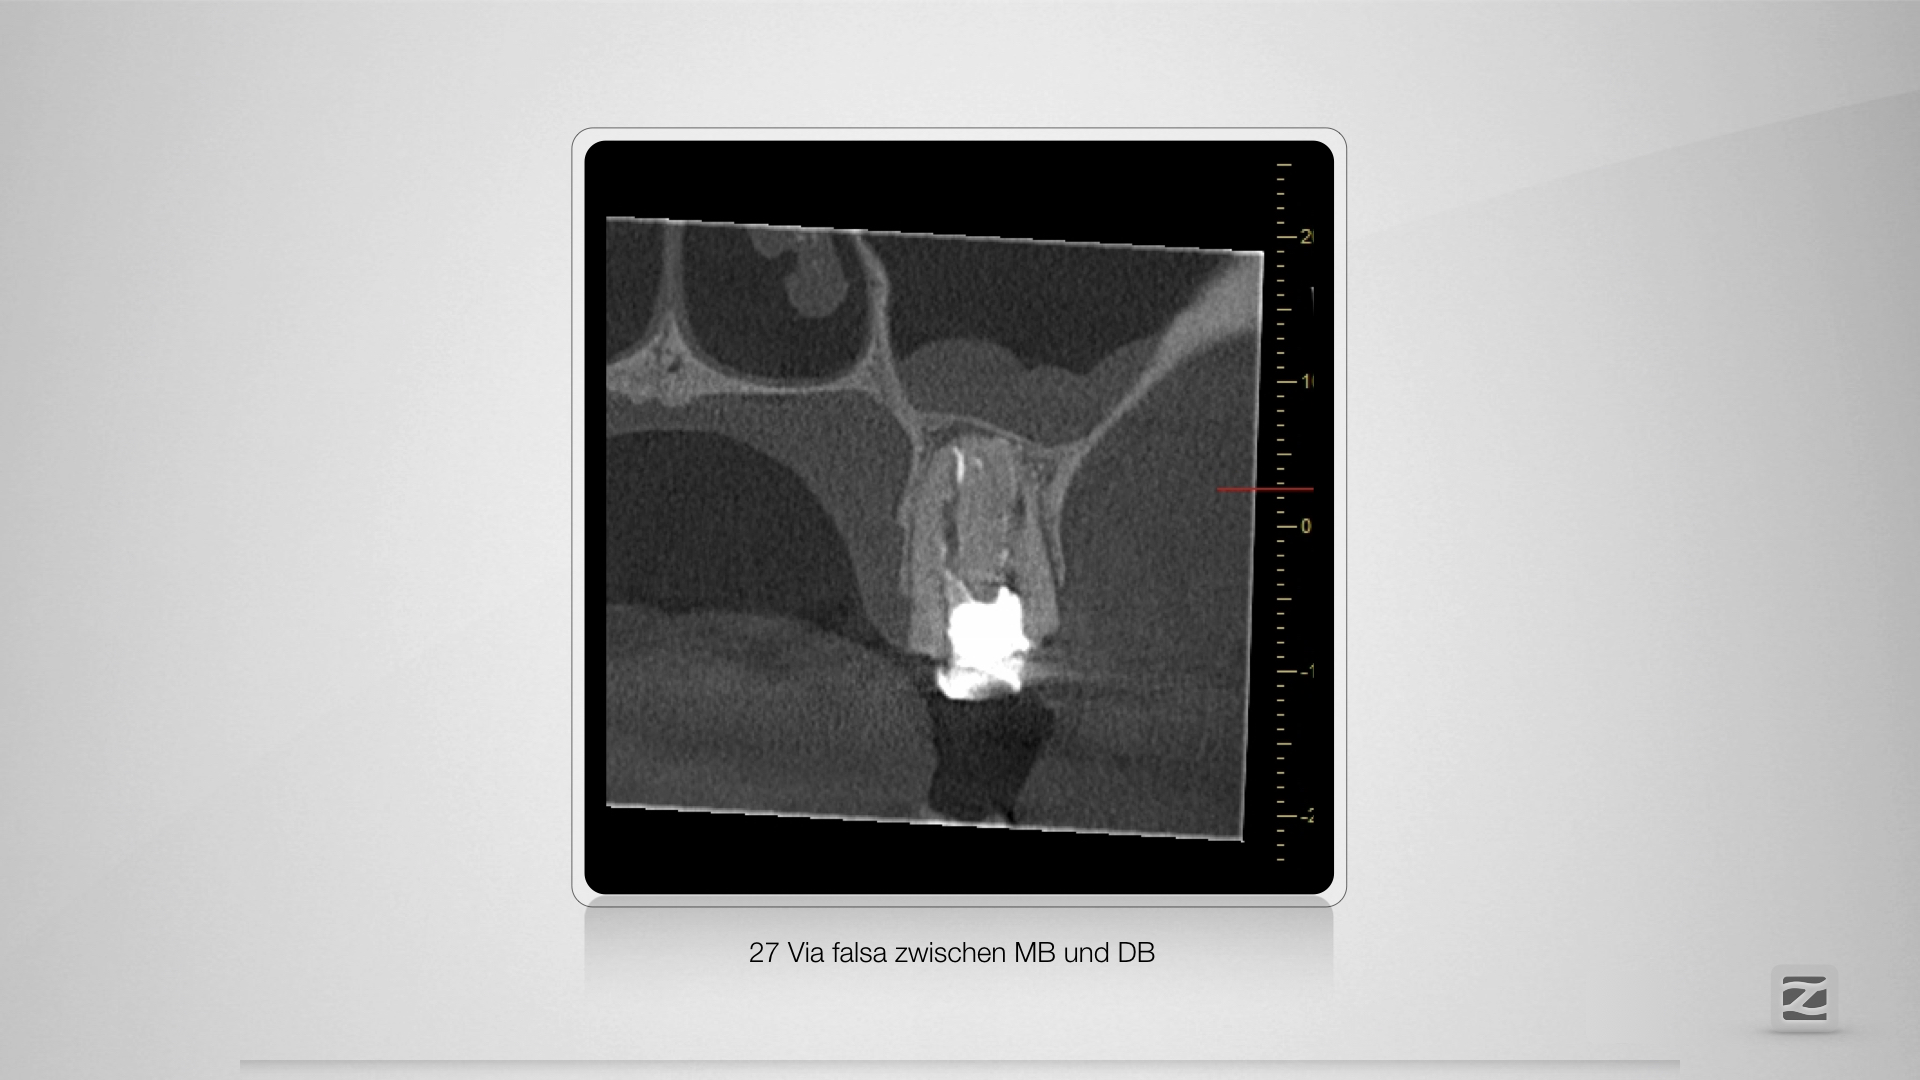

Fast getroffen ist auch vorbei!